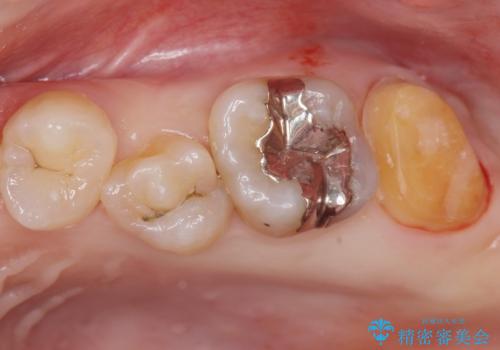

- 奥歯の歯が黒いとの事で来院された患者様です。

頬側の歯の面も粗造になっていたので、インレーではなくジルコニアクラウンでの治療となりました。